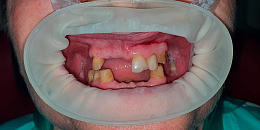

Временные композитные реставрации. Промежуточный этап в ортопедическом лечении. Выполнил врач Краснов Д.А.

До